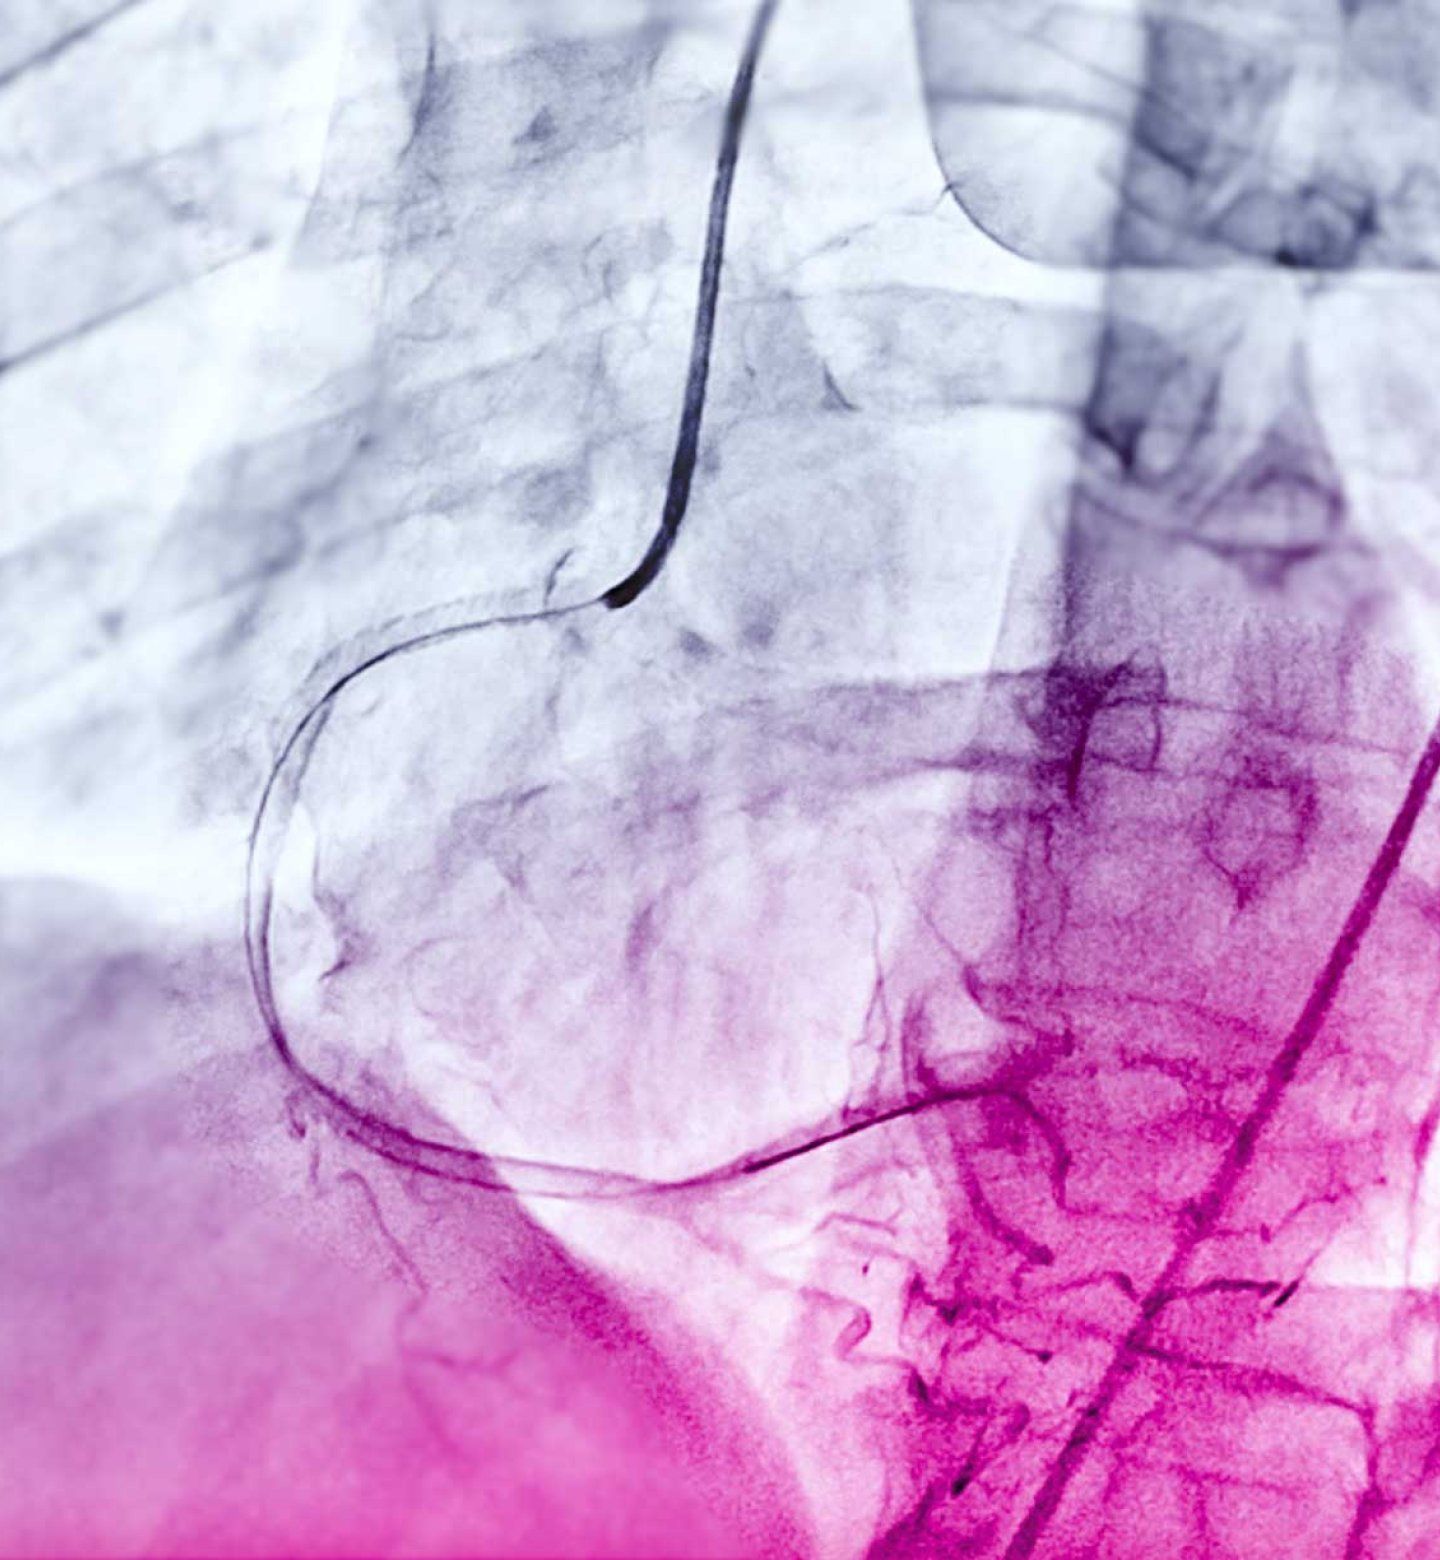

Angiograms, much like this above, could one day be used to diagnose more serious cardiac issues without further risky testing.

Physicians commonly use a test called a coronary angiogram to diagnose the condition. As part of angiograms, physicians inject a special dye into the main vessels that feed the heart to see how blood flows using x-rays. Angiograms much like this could one day be used to diagnose more serious cardiac issues without further risky testing.